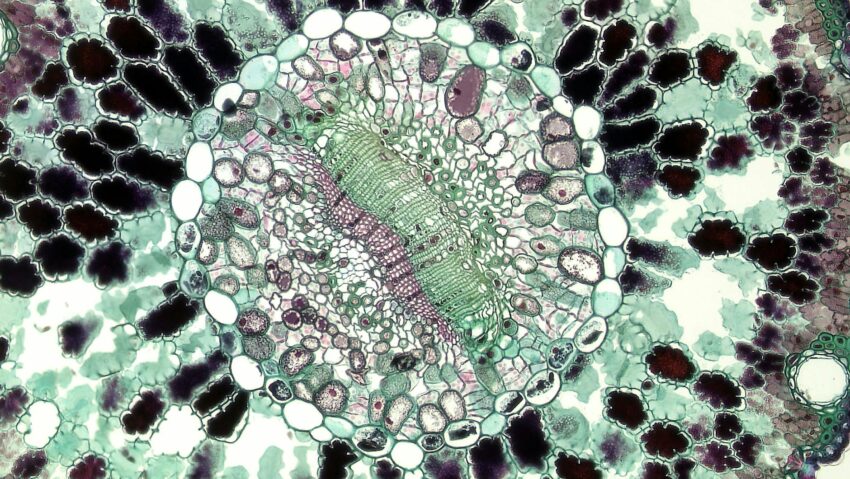

Terapiile cu celule stem sunt bazate pe capacitatea celulelor de a se transforma în diferite tipuri de țesuturi. Acest lucru permite o abordare mai precisă și mai eficientă a tratamentului, comparativ cu metodele tradiționale. Dezvoltarea acestor terapii a fost posibilă datorită progreselor în domeniul biologiei și medicinei. Cercetătorii au lucrat intens pentru a înțelege cum funcționează celulele stem și cum pot fi utilizate pentru a trata boli grave.